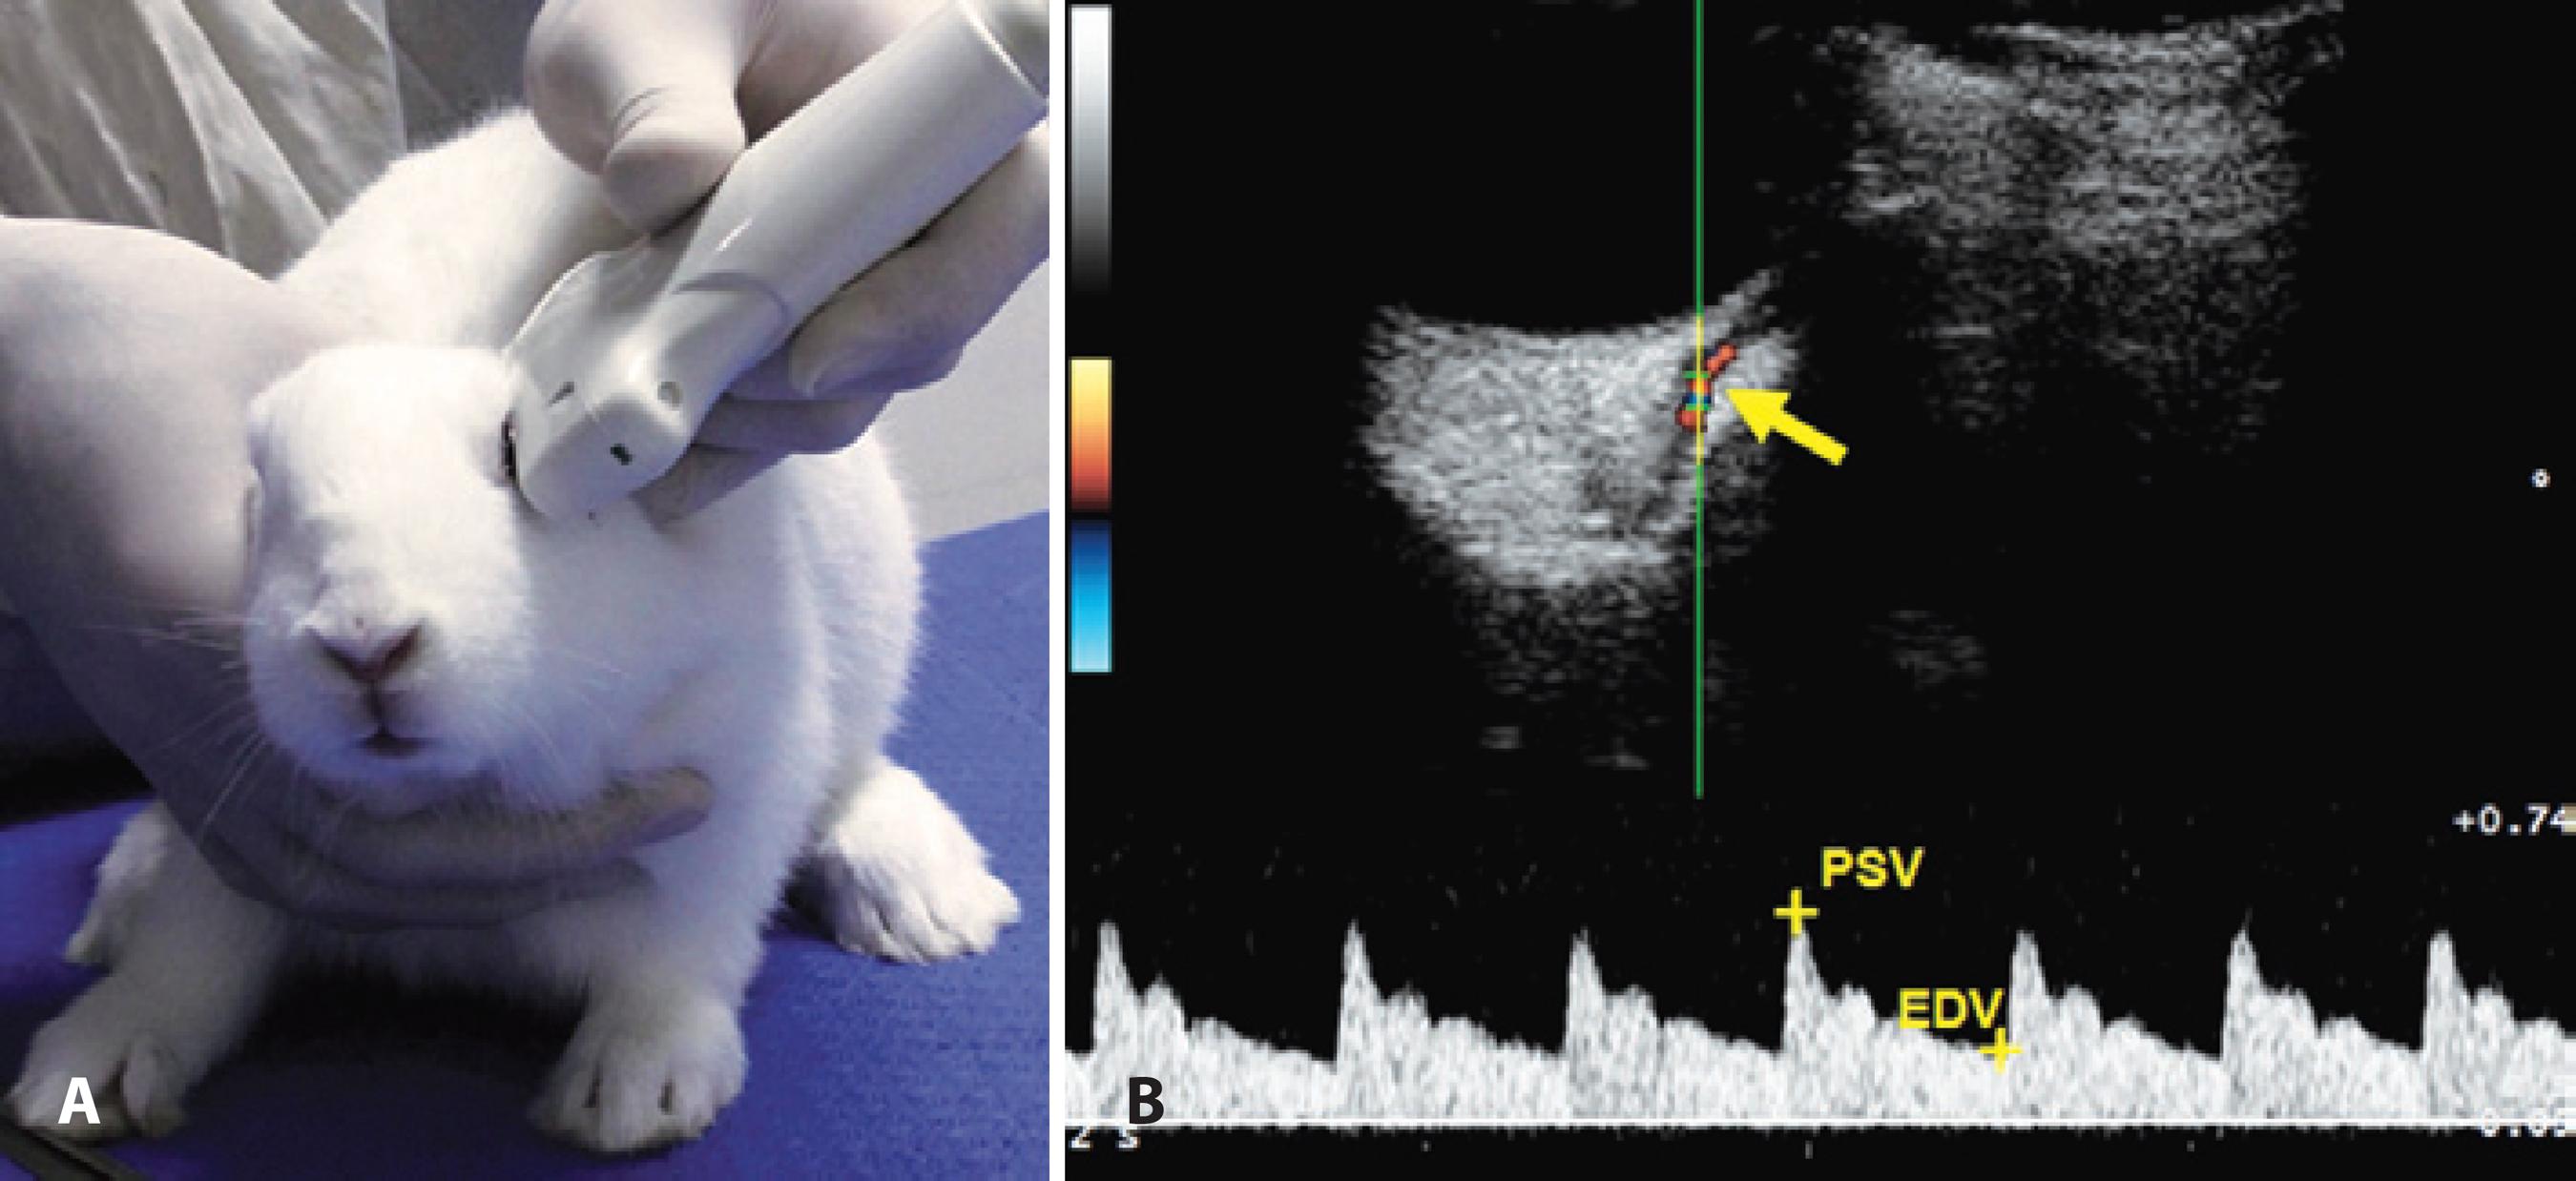

CDI was performed before and after the treatment with eye drops using an ultrasound system (MyLab 30; Esaote, Genova, Italy) equipped with a 12-MHz linear ultrasound transducer. The animals were not anesthetized, and the eye and orbit were imaged with the animal in sternal recumbency. All CDI examinations were performed by the same two people, one of whom restrained the rabbit, while the other performed the imaging. Ultrasound gel was applied to the dorsal region and to the zygomatic arch, and the transducer was gently positioned with minimal pressure in the horizontal plane after instillation of one drop of topical anesthesia (tetracaine ophthalmic drops, Anestalcon®, Alcon). The long axis of the transducer was held horizontally between the lateral and medial canthus with the marker pointing nasally (Figure 1A).

Figure 1 (A) Image of a New Zealand white rabbit during the ultrasound exam. The transducer was positioned in the horizontal plane, with the long axis of the transducer held parallel with a line connecting the medial and lateral canthus, and the marker pointing nasally. (B) The top panel shows an image of retrobulbar color Doppler imaging and pulse waveform with dicrotic notches showing blood flow velocities in a rabbit’s ophthalmic artery. Blood flow toward the ultrasound transducer was encoded in red by the power Doppler mode. The ophthalmic artery was detected and the spectral Doppler sampling volume (gate of 1 mm) was placed in the center and parallel to the imaged vessel (arrow). The bottom panel is a pulse waveform showing relative blood flow velocities.

We used the muscular cone and power Doppler mode to determine the relative position of the OA. After the detection of the blood flow by the power Doppler, the spectral Doppler sampling volume was placed in the center of the imaged vessel. The OA is readily identifiable by its characteristic dicrotic notch in the Doppler waveform associated with the closure of the aortic valve(5). The ultrasound beam and the OA were parallel, and the sample volume was set at 1 mm inside the vessel (Figure 1B). The mean values of PSV and EDV from three pulse waveforms were calculated (Figure 1B), and the RI of the blood flow was calculated using the formula [(PSV - EDV) / PSV].